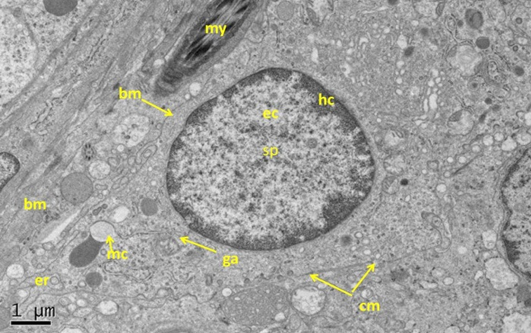

Electron micrograph (TEM) of rat testes from fresh control group (A) Showing (Left) normal cellular components